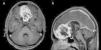

Los schwannomas son neoplasias de la vaina nerviosa originadas de las células de Schwann. Usualmente son solitarios y esporádicos, presentándose en relación a nervios periféricos, espinales o craneales. A nivel intracraneal, presentan una gran predisposición a originarse en el viii par craneal, especialmente en pacientes con neurofibromatosis tipo2. Los schwannomas de la base anterior del cráneo corresponden a menos del 1% del total de schwannomas intracraneanos. Son frecuentes en pacientes jóvenes y usualmente tienen un curso clínico benigno. Estos tumores representan un reto diagnóstico debido a su poca incidencia y sus diagnósticos diferenciales. Se han planteado varias teorías sobre su origen y desarrollo. Se presenta el caso de un paciente varón de 13años sin estigmas clínicos de neurofibromatosis, con un cuadro de cefalea, dolor ocular, papiledema y disminución de la agudeza visual en el cual se documentó un tumor único ubicado en la fosa craneal anterior. Se realizó una resección completa de la masa tumoral, cuyo diagnóstico histopatológico fue de schwannoma, y presentó una recuperación clínica de todos sus síntomas. En una revisión bibliográfica se ubicó un total de 66 pacientes reportados a nivel mundial con este diagnóstico. Se describen sus características epidemiológicas y clínicas más relevantes, así como la relación con los tumores de las células de la vaina olfatoria, una entidad descrita recientemente y que presenta gran similitud.

Schwannomas are nerve sheath tumours that originate in Schwann cells. They are usually solitary and sporadic and manifest on peripheral, spinal or cranial nerves. Intracranial schwannomas tend to manifest on the eighth cranial nerve, particularly in patients with neurofibromatosis type2. Anterior skull-base schwannomas represent less than 1% of all intracranial schwannomas. They are more frequent in young people and are typically benign. These tumours represent a diagnostic challenge due to their rarity and difficult differential diagnosis, and numerous theories have been postulated concerning their origin and development. In this article, we present the case of a 13-year-old male with a single anterior cranial-base tumour not associated with neurofibromatosis who presented with headache, papilloedema, eye pain and loss of visual acuity. Complete resection of the tumour was performed, which was histopathologically diagnosed as a schwannoma. The patient made a complete clinical recovery with abatement of all symptoms. We conducted a review of the literature and found 66 cases worldwide with this diagnosis. We describe the most relevant epidemiological and clinical characteristics of this kind of tumour and its relation with the recently discovered and similar olfactory schwannoma.